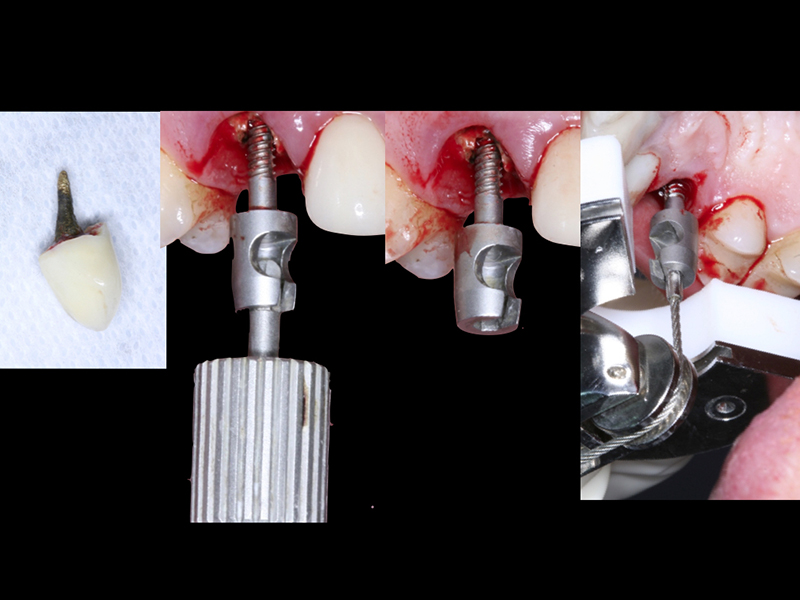

- Cirurgia de Instalação dos Implantes: Os implantes são fixados no osso maxilar ou mandibular, proporcionando uma base sólida para a prótese.

- Fixação da Prótese: Em até 72 horas após a cirurgia, a prótese provisória é instalada, permitindo que o paciente recupere a funcionalidade e a estética imediatamente.